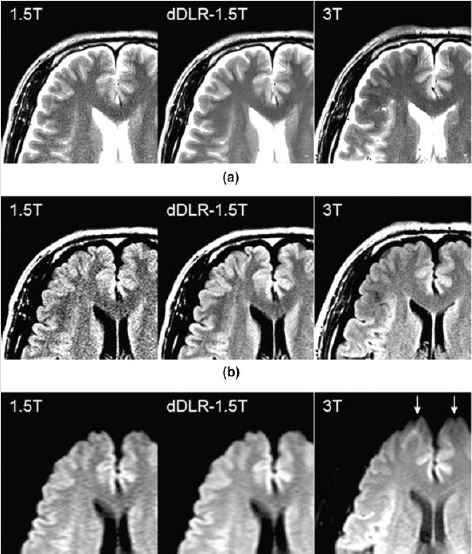

В 11 здорових добровольців було проскановано головний мозок на обох системах для отримання зображень T2WI, FLAIR і DWI на МРТ-системах 1,5T та 3T.

Штучні нейронні мережі на основі глибокого навчання (AiCE) застосовували до зображень отриманих на МРТ 1,5T, а якість зображення оцінювали якісно та кількісно за допомогою індексу подібності структури, співвідношень сигнал/шум та контраст/шум, а також опитуючи лікарів-радіологів стосовно візуальної якості отриманих зображень.

Візуальна якість зображення, співвідношення сигнал/шум і контраст/шум покращились в зображеннях отриманих на 1,5T після застосування AiCE для всіх послідовностей, дорівнюючи або навіть перевищуючи ці показники у зображень отриманих на МРТ 3T.

DWI-зображення отримані на МРТ 1,5T з AiCE мають менше спотворень і значно вищі показники співвідношень сигнал/шум і контраст/шум між смугастим тілом і білою речовиною, ніж зображення отриманні на МРТ 3T.

Використання AiCE при скануванні головного мозку на МРТ- системі з потужністю магнітного поля 1,5T призвело до покращення якості зображення, збільшення співвідношень сигнал/шуму та контраст/шум між внутрішньомозковими структурами порівняно з оригінальними зображеннями.

Ці зображення вважалися еквівалентними або навіть кращими за зображення отримані на МРТ-системі 3T.